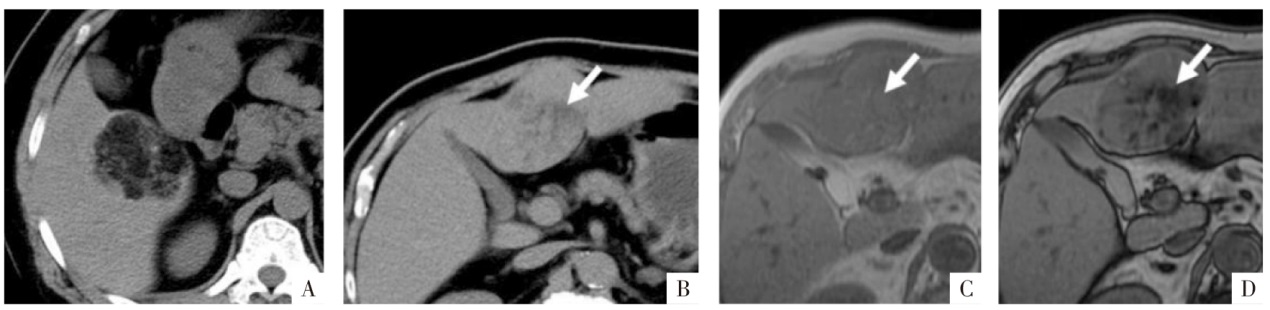

图4

病人女,42岁。手术病理证实为肝左外叶上皮样血管平滑肌脂肪瘤(细箭),内有直径约5 mm小块脂肪(粗箭)。A、B图分别为厚层同相位及反相位影像,层厚6 mm,矩阵256×180,同相位影像上含脂区域呈高信号(A),反相位影像上为含脂区域整体信号衰减(B),易误判为脂肪变性;C图为薄层高分辨力反相位影像,层厚3 mm,矩阵320×288,含脂区域中心仍呈高信号,周围可见勾边,为小脂肪块的典型表现。